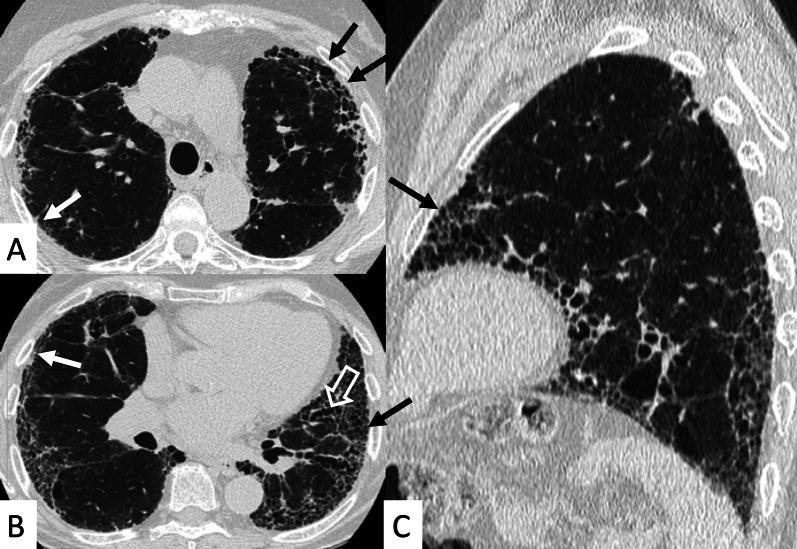

Connective tissue diseases (CTDs) include a spectrum of disorders that affect the connective tissue of the human body; they include autoimmune disorders characterized by immune-mediated chronic inflammation and the development of fibrosis. Lung involvement can be misdiagnosed, since pulmonary alterations preceded osteo-articular manifestations only in 20% of cases and they have no clear clinical findings in the early phases. All pulmonary structures may be interested: pulmonary interstitium, airways, pleura and respiratory muscles. Among these autoimmune disorders, rheumatoid arthritis (RA) is characterized by usual interstitial pneumonia (UIP), pulmonary nodules and airway disease with air-trapping, whereas non-specific interstitial pneumonia (NSIP), pulmonary hypertension and esophageal dilatation are frequently revealed in systemic sclerosis (SSc). NSIP and organizing pneumonia (OP) may be found in patients having polymyositis (PM) and dermatomyositis (DM); in some cases, perilobular consolidations and reverse halo-sign areas may be observed. Systemic lupus erythematosus (SLE) is characterized by serositis, acute lupus pneumonitis and alveolar hemorrhage. In the Sjögren syndrome (SS), the most frequent pattern encountered on HRCT images is represented by NSIP; UIP and lymphocytic interstitial pneumonia (LIP) are reported with a lower frequency. Finally, fibrotic NSIP may be the interstitial disease observed in patients having mixed connective tissue diseases (MCTD). This pictorial review therefore aims to provide clinical features and imaging findings associated with autoimmune CTDs, in order to help radiologists, pneumologists and rheumatologists in their diagnoses and management.

结缔组织病(CTDs)包括一系列影响人体结缔组织的疾病;它们包括以免疫介导的慢性炎症和纤维化发展为特征的自身免疫性疾病。肺部受累可能会被误诊,因为肺部改变仅在20%的病例中先于骨关节炎表现出现,且在早期阶段没有明确的临床发现。所有肺部结构都可能受累:肺间质、气道、胸膜和呼吸肌。在这些自身免疫性疾病中,类风湿关节炎(RA)的特征是普通型间质性肺炎(UIP)、肺结节和伴有空气潴留的气道疾病,而系统性硬化症(SSc)常表现为非特异性间质性肺炎(NSIP)、肺动脉高压和食管扩张。NSIP和机化性肺炎(OP)可见于多发性肌炎(PM)和皮肌炎(DM)患者;在某些情况下,可观察到小叶周围实变和反晕征区域。系统性红斑狼疮(SLE)的特征是浆膜炎、急性狼疮性肺炎和肺泡出血。在干燥综合征(SS)中,HRCT图像上最常见的表现是NSIP;UIP和淋巴细胞间质性肺炎(LIP)的报道频率较低。最后,纤维化NSIP可能是混合性结缔组织病(MCTD)患者中观察到的间质性疾病。因此,本图像综述旨在提供与自身免疫性CTDs相关的临床特征和影像学表现,以帮助放射科医生、呼吸科医生和风湿病科医生进行诊断和管理。